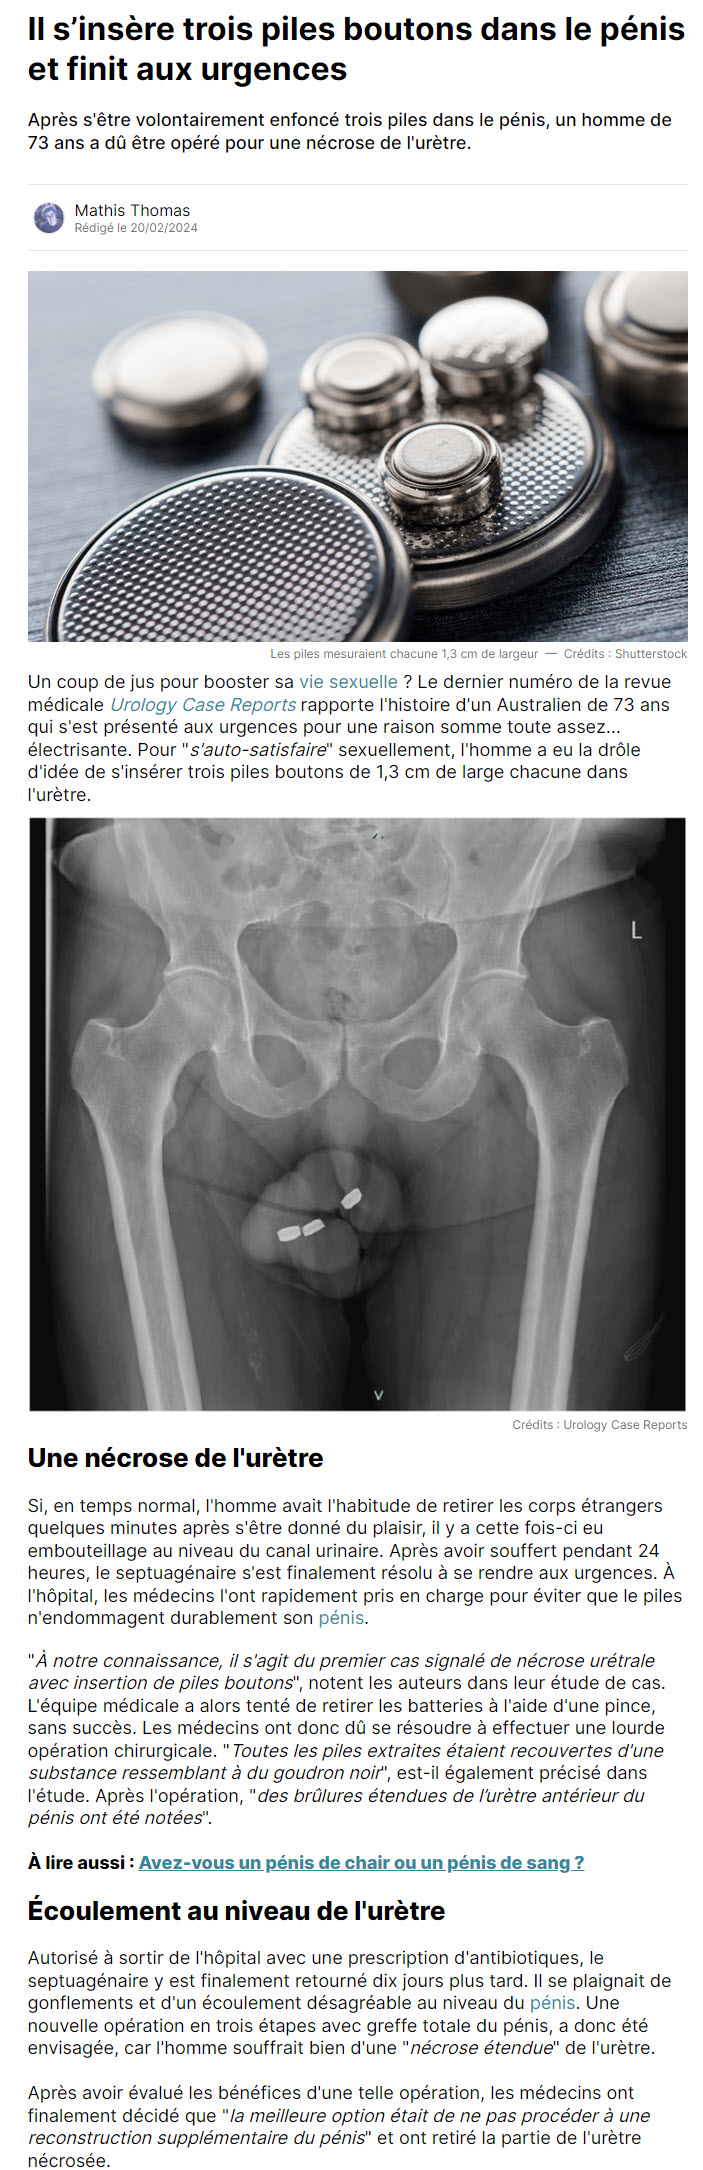

Dans un cas médical inhabituel, un Australien de 73 ans s'est retrouvé aux urgences après une tentative extrême d'auto-satisfaction sexuelle. L'homme avait inséré trois piles boutons dans son urètre, une pratique qui s'est soldée par une nécrose nécessitant une intervention chirurgicale d'urgence. Habituellement capable de retirer de tels objets après usage, il s'est trouvé dans l'incapacité de le faire cette fois-ci, provoquant un blocage et des dommages sévères à son urètre.